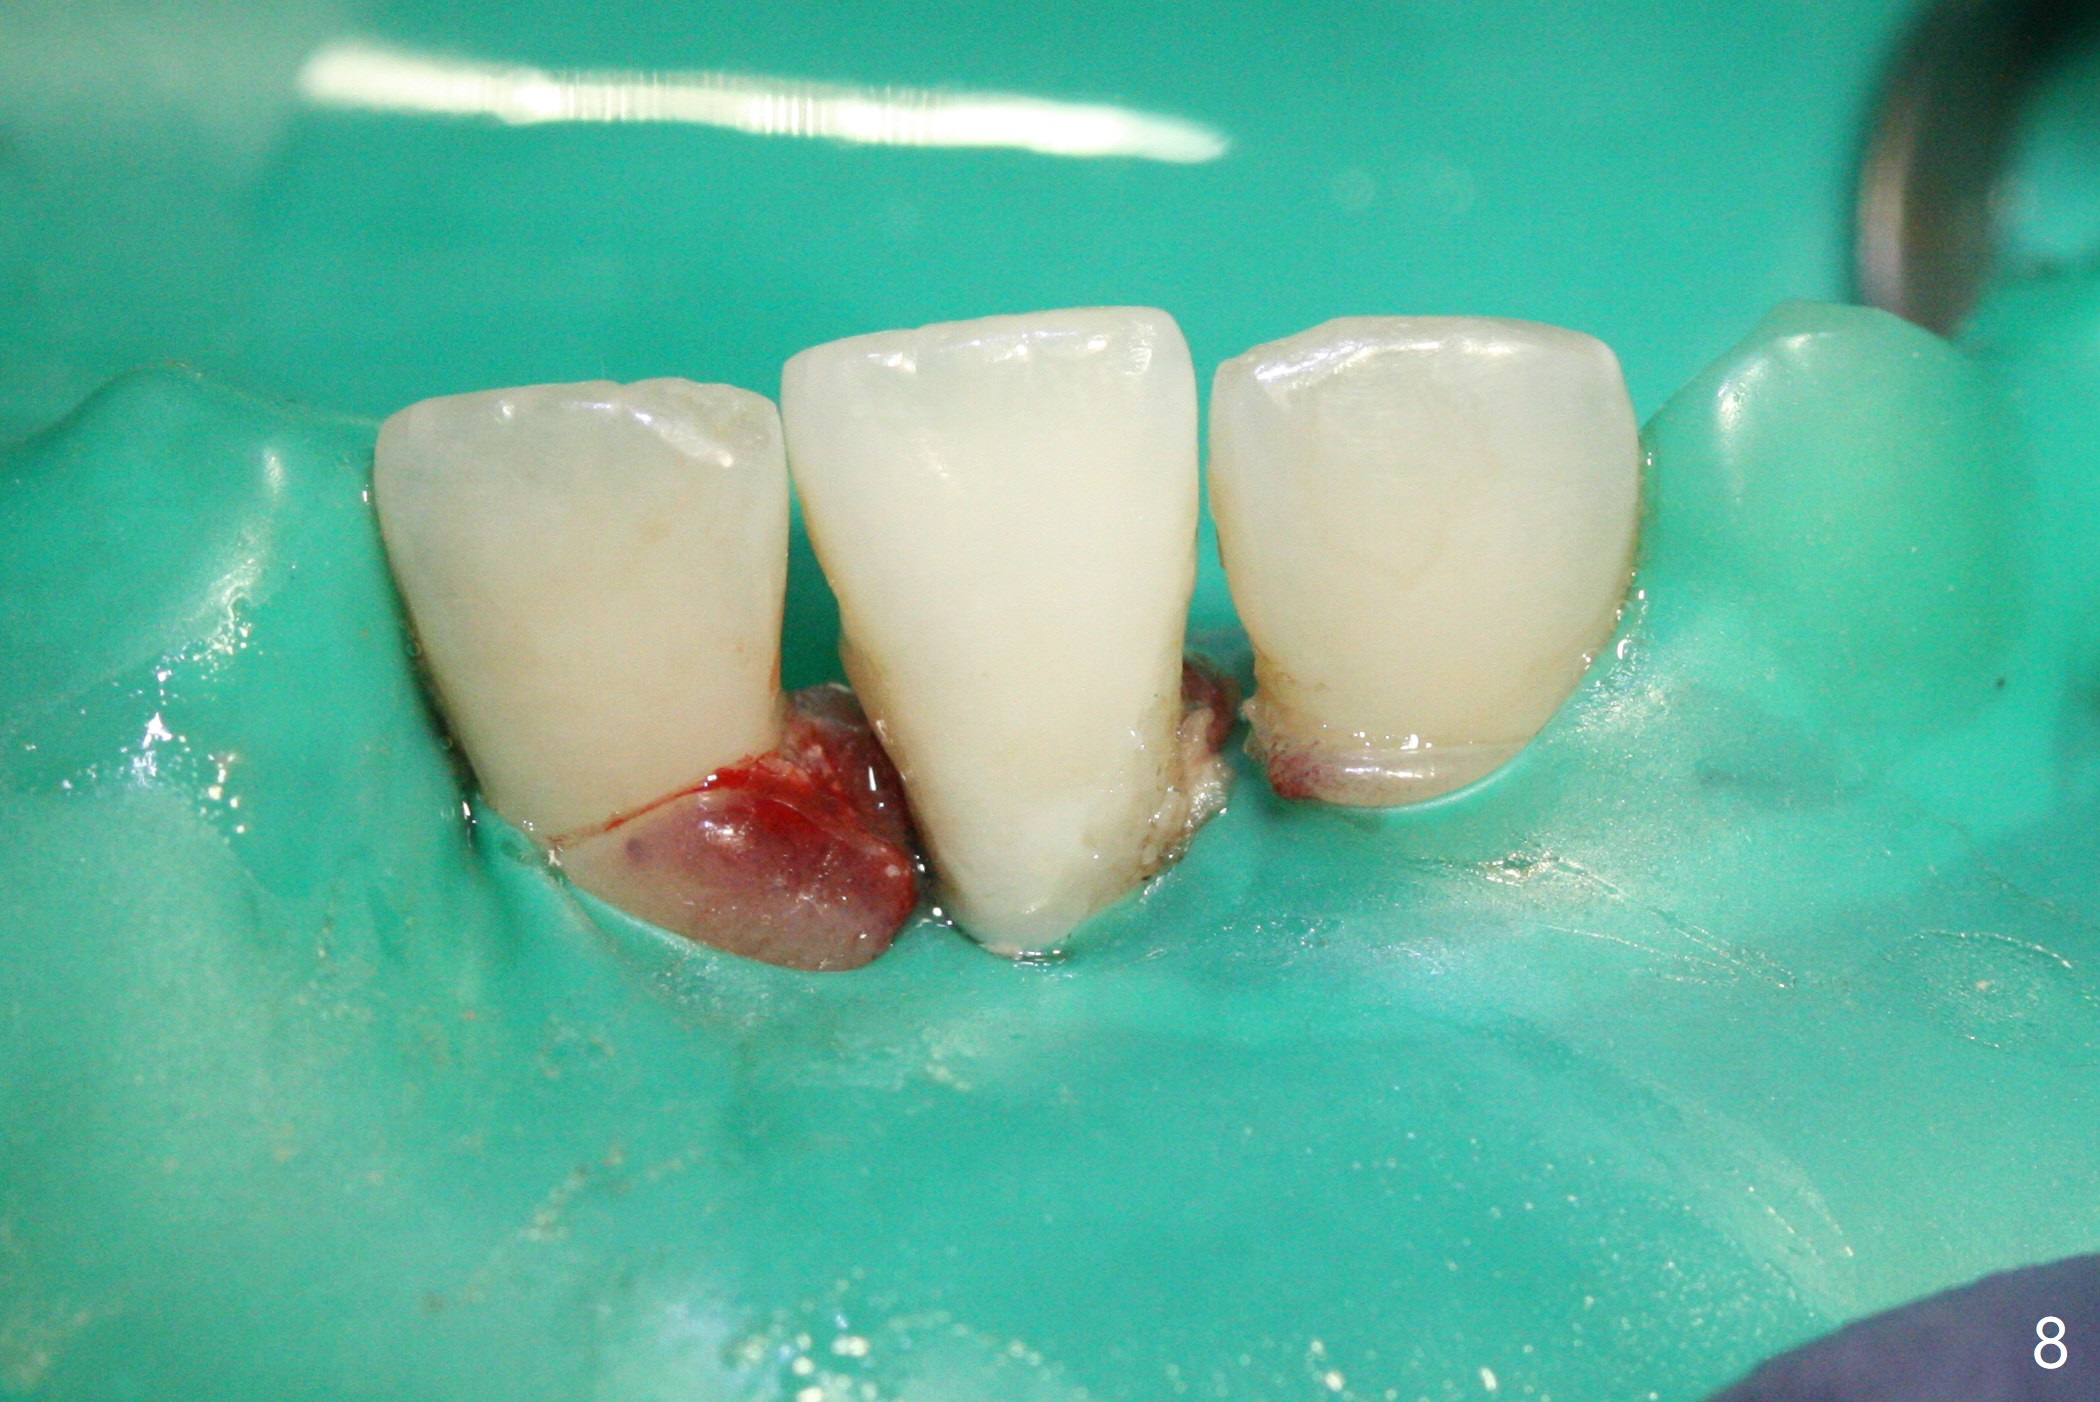

A 31-year-old woman fractured the lower left central incisor when it was hit by her 2-year-old son's head with mesiobuccal subgingival margin (Fig.1). After RCT (Fig.2), gingivectomy is conducted with eletrosurg to expose the fractured margin (Fig.3). In 2 days, a prefabricated fiber post will be bonded with the tooth and the fractured fragment together. To extend the use of the incisor, two implants are required (Fig.4). As scheduled, the patient returns with the fractured portion (Fig.5,6 (buccal (B) and lingual (L) views)). The periodontal dressing is in place (Fig.7 P). After preparation of the post space, the fiber post (Fig.10 (P)) is bonded with resin cement (Fig. 10 ^ and *) to the tooth and fragment with rubber dam (Fig.8). The patient is pleased post occlusal adjustment (Fig.9).